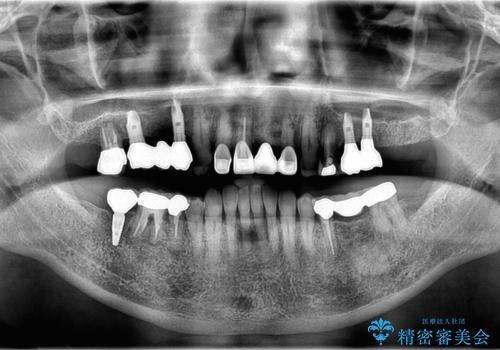

- 「他院で治療した被せ物が外れた」を主訴に来院された患者様です。診査診断を行い歯の保存が困難だったため抜歯後、インプラントで治療しました。

インプラントを入れるためには十分な骨の高さと幅が必要です。術前に検査を行い必要であれば別途、骨や角化歯肉を増やす治療も行う事があります。

インプラントの土台と被せ物は適合が良い物を制作するため、シリコン印象材を使用し型を取っています。